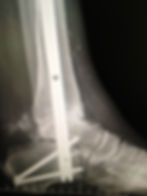

Total Ankle Joint Replacement

Ankle Fusion

Foot and Ankle Trauma